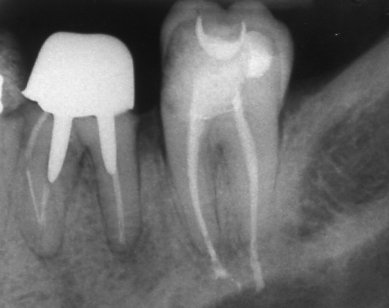

Запълване с препресване

Ендодонтия